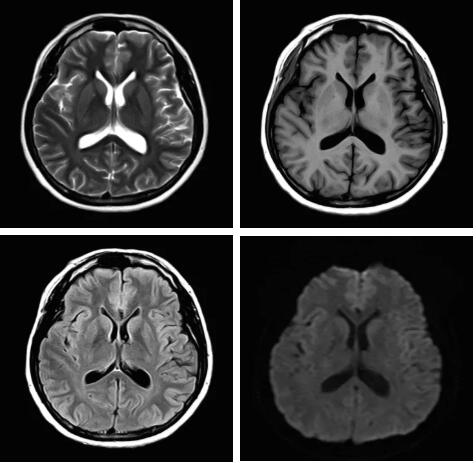

見所未見 微小腫瘤無(wú)處遁藏——

“螢火蟲”成像技術(shù) 顱內(nèi)腫瘤微小病灶檢出新發(fā)現(xiàn)

此技術(shù)主要用于神經(jīng)系統(tǒng)惡性腫瘤,以及其他腫瘤腦轉(zhuǎn)移瘤篩查。傳統(tǒng)情況下做腫瘤腦轉(zhuǎn)移篩查,很容易漏掉5mm以下小病灶,臨床發(fā)現(xiàn)后干預(yù)治療比較晚,要實(shí)現(xiàn)2mm高空間分辨率和超薄層全腦掃描在保證信噪比的情況下需要很長(zhǎng)時(shí)間大概十多分鐘,而且薄層增強(qiáng)序列顱內(nèi)血管呈高亮信號(hào),會(huì)干擾顱內(nèi)小病灶的觀察,血管和小病灶區(qū)分困難。佳能”螢火蟲”成像技術(shù)既可以實(shí)現(xiàn)高空間分辨率和超薄層(最薄可實(shí)現(xiàn)0.2mm)全腦掃描,掃描時(shí)間短,2-3分鐘即可實(shí)現(xiàn)全腦3D掃描,同時(shí)避免了血管高亮信號(hào)的干擾,對(duì)顱內(nèi)原發(fā)或繼發(fā)的微小腫瘤檢查有重大意義。“螢火蟲”成像技術(shù)具有磁敏感效應(yīng),對(duì)于亞急性血敏感敏感,可以區(qū)分出血和強(qiáng)化的腫瘤。